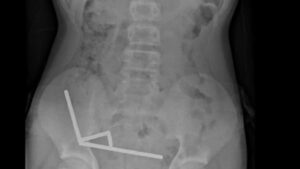

Quando chegou ao hospital, exames mostraram que os ímãs haviam se agrupado dentro do abdômen, unindo diferentes partes do trato intestinal.

Durante o procedimento, a equipe cirúrgica encontrou correntes de ímãs aderidas entre o intestino delgado e o grosso. A força magnética prolongada interrompeu a circulação sanguínea em alguns trechos, provocando necrose tecidual.